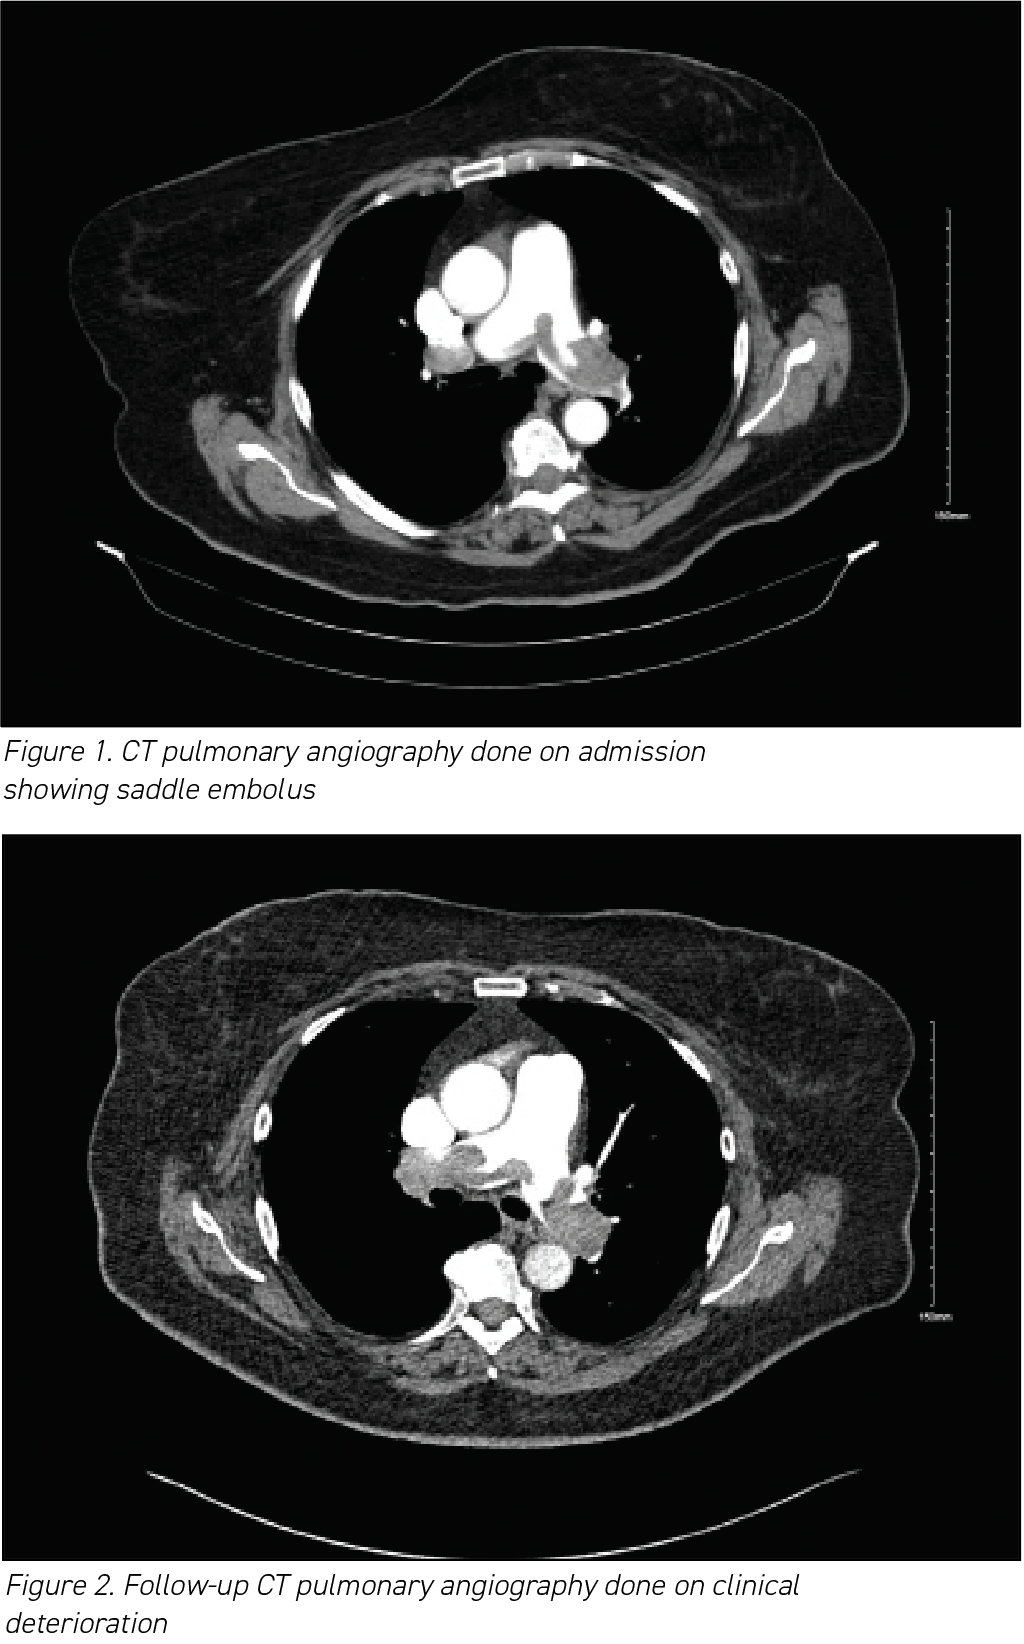

Here, we present a case of SPE in a tertiary care setting, providing insights into its clinical presentation and management. The patient, a woman in her 70s, presented with abrupt-onset dyspnoea, chest tightness and dizziness. Elevated D-dimers prompted a CT pulmonary angiography, revealing a saddle thrombus with bilateral emboli. Although initial anticoagulation therapy showed limited improvement, thrombolysis resulted in significant recovery. The patient was subsequently transitioned to a direct oral anticoagulant (DOAC) and discharged with plans for ongoing monitoring. This case highlights the complexities involved in successful management strategies for SPE, offering valuable insights for clinicians.